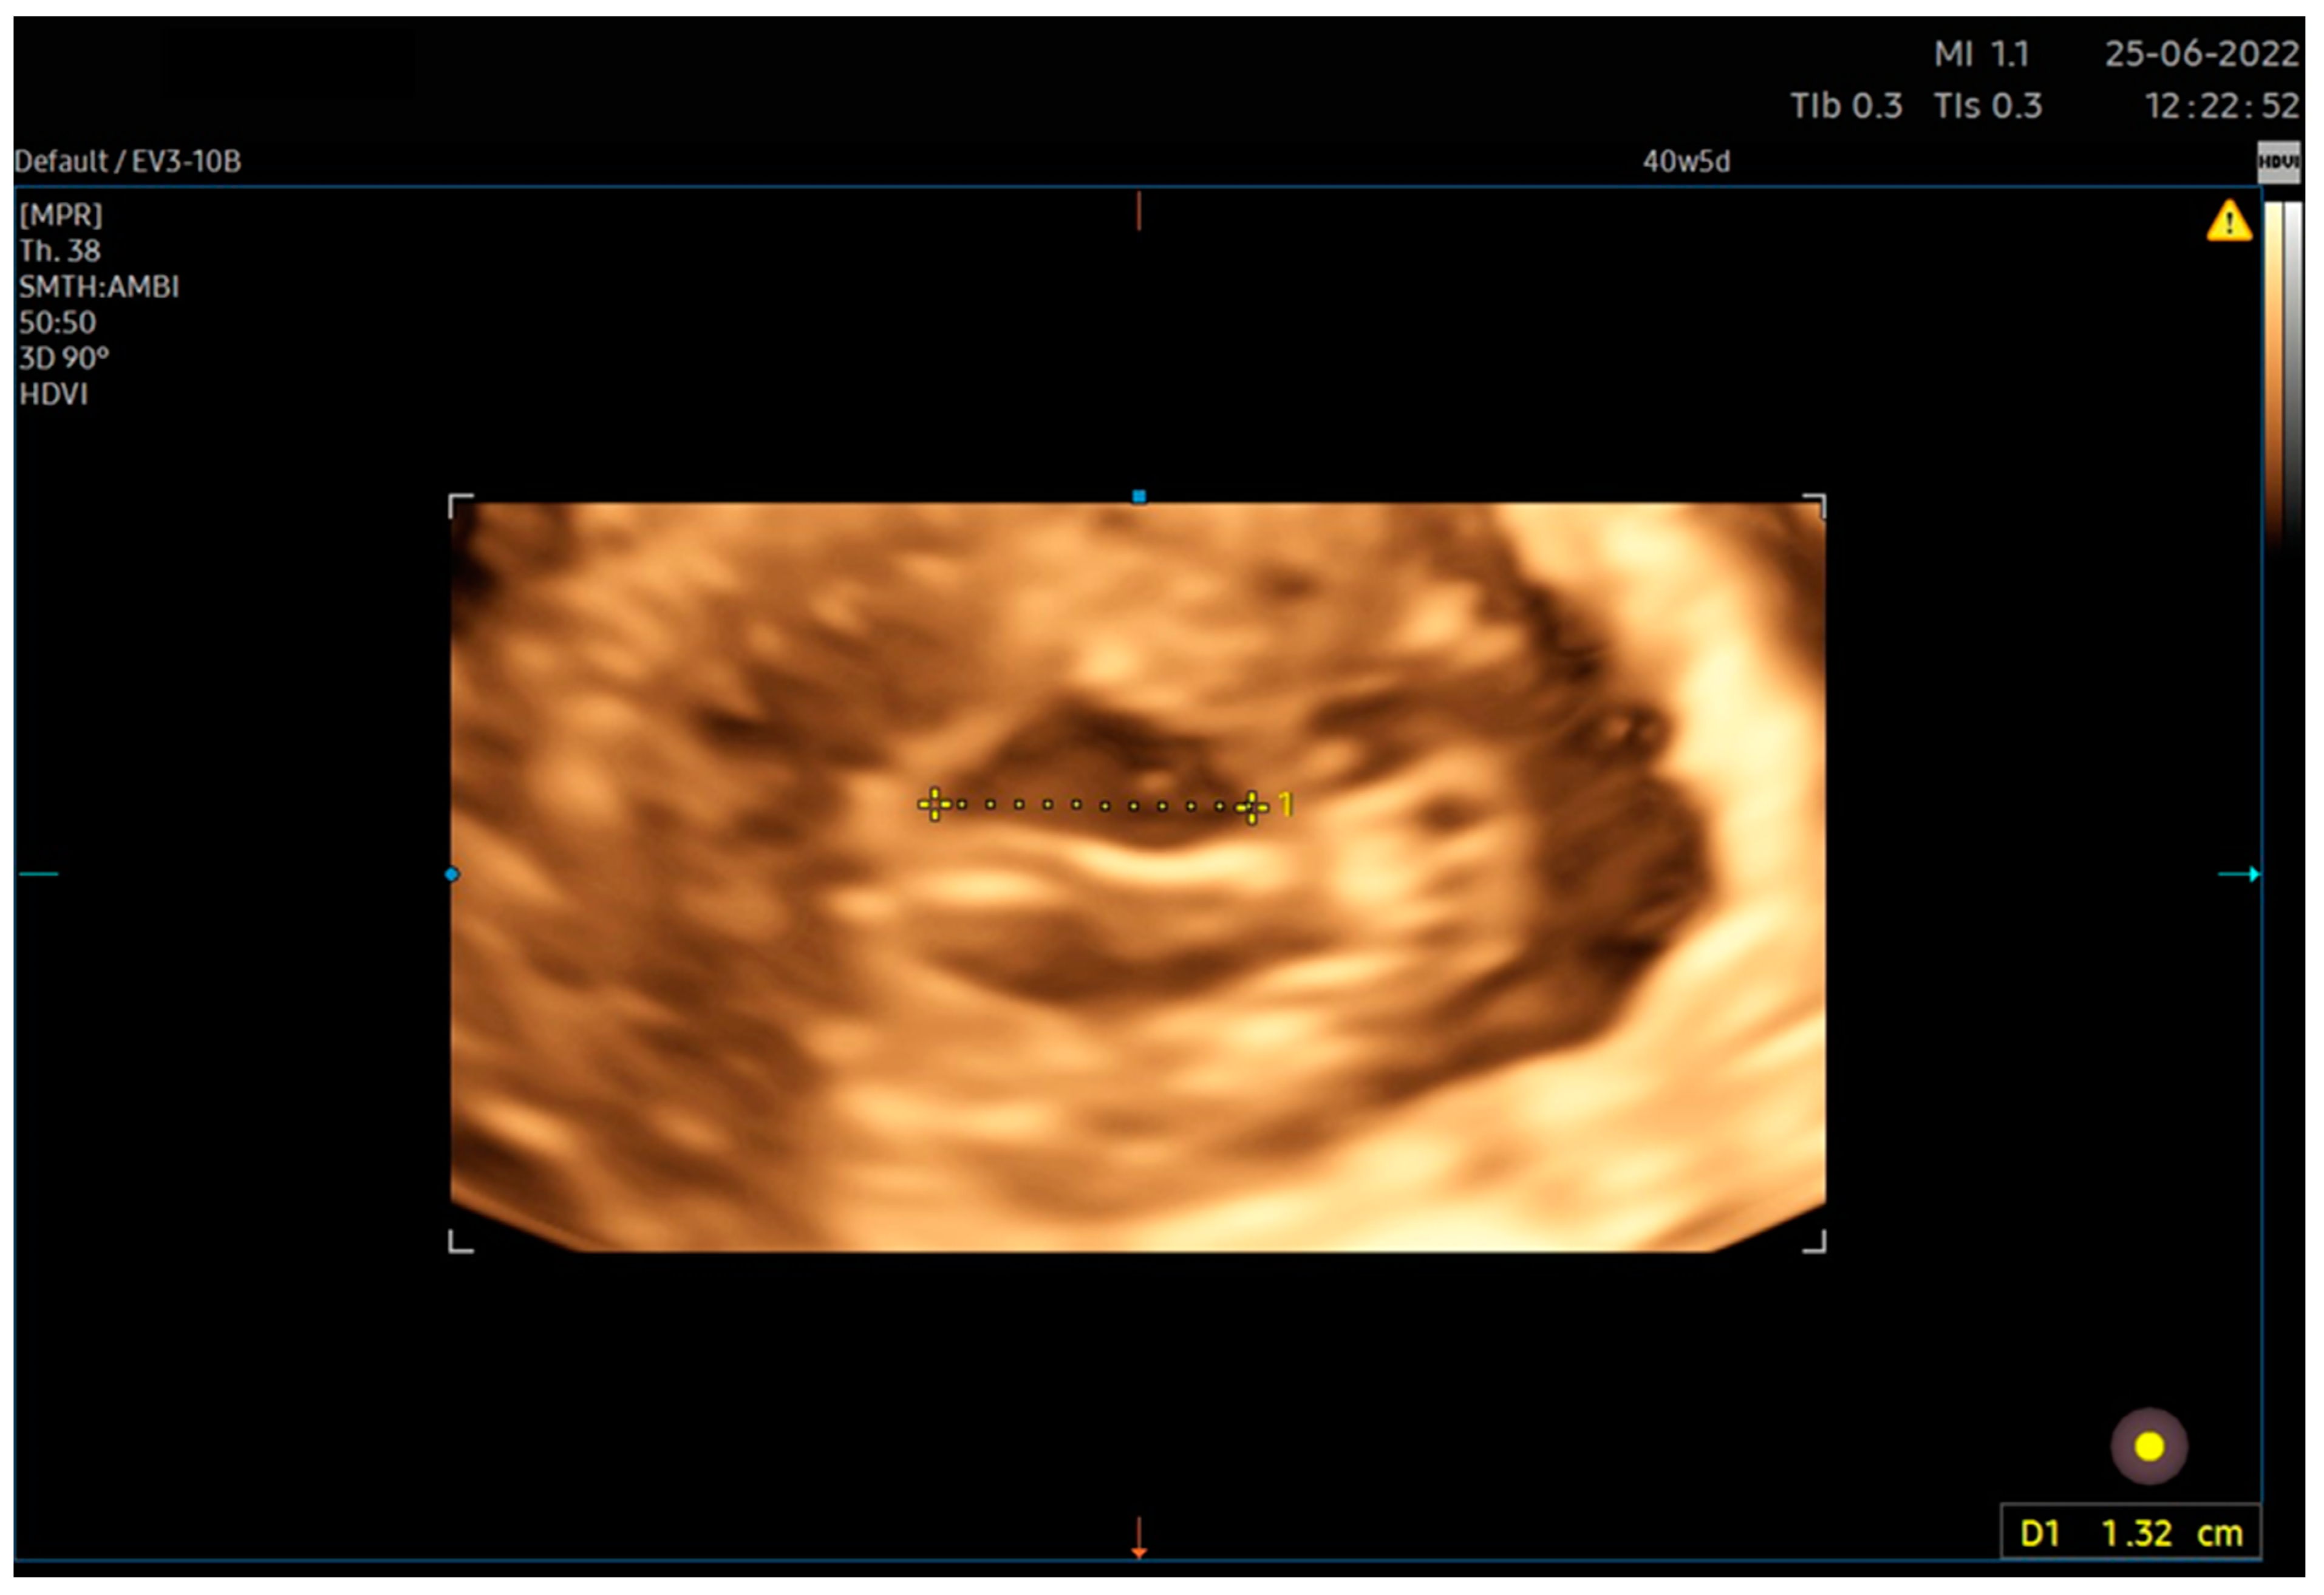

| 6. After calculating the E-Cervix parameters, volumetric image acquisition of the cervix was performed. The 3D image was rotated so that the external os of the cervix was presented en face on the screen; then, we measured the widest dimension of the external cervical os (dilatation—Figure 1). 7. We withdrew the transducer to the area of the vaginal os. 8. The transducer was placed in the vaginal axis; the vagino–cervical angle (VCA) measurement was performed after turning on the “central transducer line” option; the second line was guided tangentially to the axis of the cervical canal. In the case of a bent canal, the line was drawn tangentially to the end part contacting the vagina. We measured the angle formed at the intersection of the abovementioned lines (Figure 3). 9. We measured the AoP with the transducer located near the vaginal opening by drawing two lines—tangent to the long axis of the cross-section through the pubic symphysis and through the bone point of the fetal head being the most advanced in the birth canal (Figure 2). |